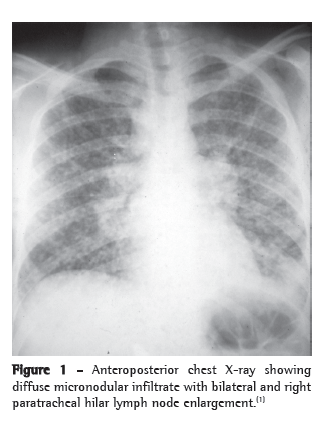

Radiological tests are not specific for histoplasmosis. In acute pulmonary histoplasmosis, the most common radiological finding is the presence of bilateral and mediastinal hilar lymph node enlargement associated with bilateral perihilar reticulonodular infiltrate (Figure 1). However, unilateral hilar lymph node enlargement, diffuse reticulonodular interstitial infiltrate, cavitation and diffuse or isolated nodules can be found. In chronic pulmonary histoplasmosis, the radiological findings are similar to those in adult or reinfection tuberculosis, that is, progressive infiltrate in the upper lobe, cavitation and signs of fibrosis. Mediastinal enlargement can be seen principally on CT scans of the chest of patients with granulomatous histoplasmosis and mediastinal fibrosis. The presence of a solitary nodule or multiple nodules with central calcification is quite characteristic of the nodular form, that is, of histoplasmoma.(1-5)

The so-called acute or epidemic pulmonary histoplasmosis presents to clinicians as isolated cases of difficult diagnosis or as microepidemics of easier diagnosis and benign course, the symptoms of which depend on the degree of exposure to the infective propagules. Fever, persistent and mildly productive cough, headache, asthenia, retrosternal pain and severe prostration are common. Pallor is a characteristic sign. Enlargement of superficial lymph nodes and hepatosplenomegaly are characteristic findings in the acute diffuse pulmonary form. Pulmonary physical signs are insignificant. The incubation period ranges from 3 to 14 days. The most common radiological findings in this form are bilateral hilar lymph node enlargement and bilateral reticulonodular infiltrate. When hilar lymph node enlargement is unilateral, this aspect is indistinguishable from the primary complex of pulmonary tuberculosis.(2,5-8)